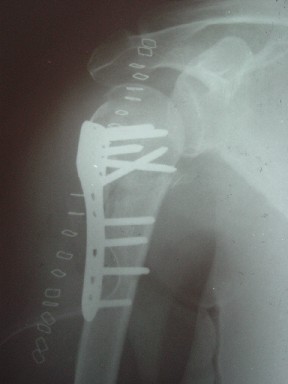

Re: Перелом шейки плеча

сделать закрытую репозицию с помощью ЭОПа совсем не сложно, после этого еще проще провести 3-6 спиц и получить красивую рентгенограмму. Есть только небольшая проблема это ROTATOR CUFF. Для плечевого сустава только костное восстановление не достаточно. для функции плечевого сустава нужны вращатели.

Давайте представим себе состояние манжетки вращателей после вывиха плеча, а еще и с отрывным переломом бугров. Головка может и прирастет, еесли не будет аваскулярного некроза, но хорошего функционального результата не ждите.

Висеть будет красиво. У людей физически активного периода жизни нужно открыть, восстановить костную анатомию и восстановить сухожильный аппарат.

В этом плане Locking plate очень хороша так как позволяет начать движения сразу после операции.

Клинические снимки - 3 недели после операции